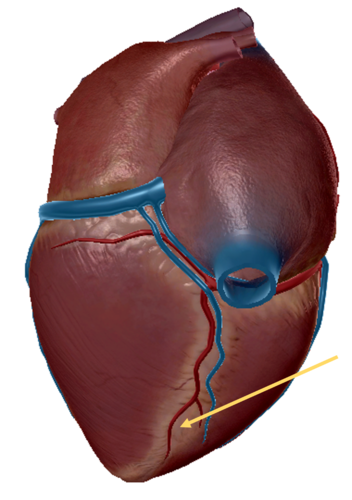

anterior inter ventricular sulcus

right coronary artery

circumflex artery

great cardiac vein

middle cardiac vein

anterior inter ventricular artery

left pulmonary veins

left pulmonary artery

posterior interventricular sulcus

small cardiac vein